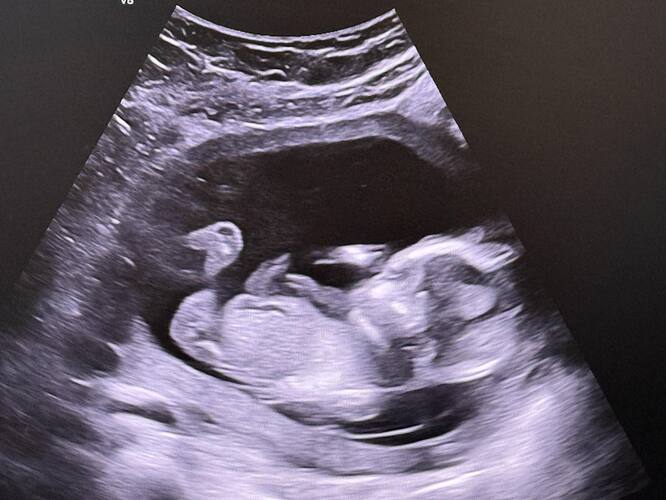

Ben benim çocugun iki defadır alamıyorum çünkü hep sırtını dönüp bacagını kapatıyor şuan 14 haftalıgız göremedi henüz

varsa tahminler albilirim ![]()

Bacak arası fazla gözükmüyor birde çok net değil ama duruş kız bebek gibi canım farklı net fotoğrafi var mı tekrar at bakayım

Baktım canım ama net fotoğraf atarsa tekrar bakarım

Kese şekli duruşu erkek bebek gibi ama sonraki attığına bir daha baktım kız gibi başka net var mı canım senin ki sürpriz bebek çözemedim ![]()